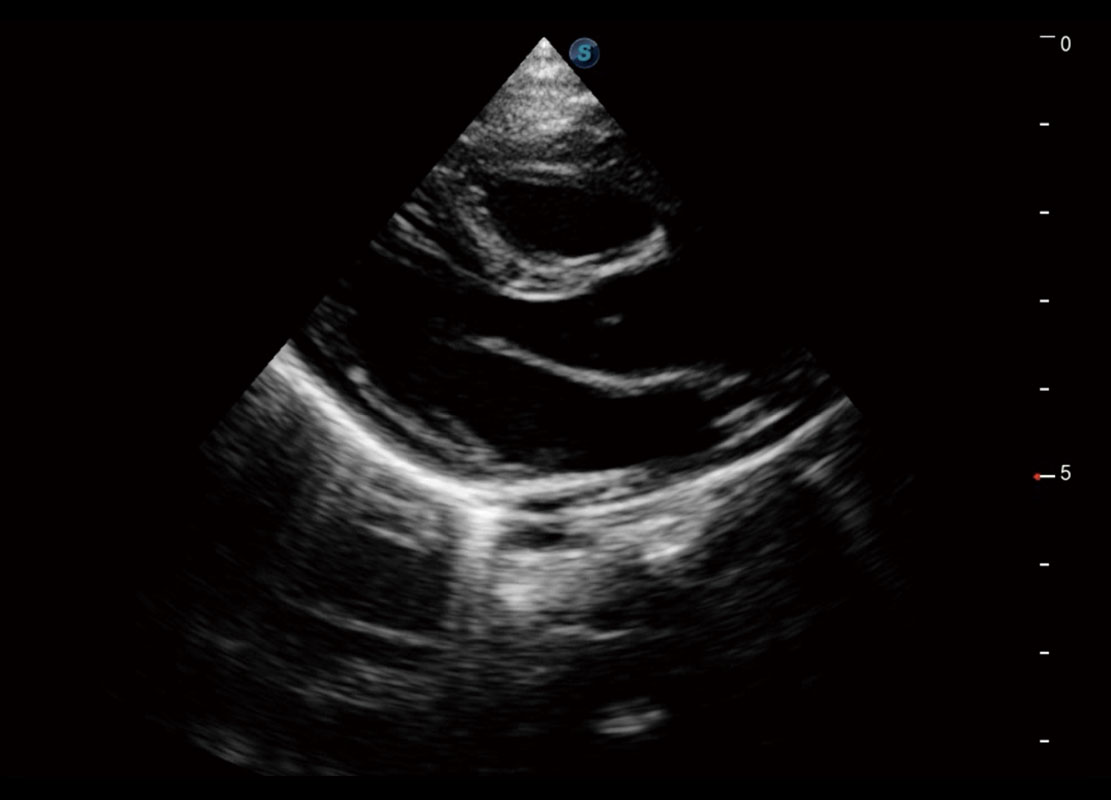

P60搭载宽频带线阵探头、宽景成像、弹性成像技术,为您提供乳腺应用方案。P60支持高频相控阵探头、线阵探头、腹部高频探头、腹部微凸探头等,丰富的探头群搭载敏感的彩色血流成像,适用于新生儿多种脏器检测要求,满足新生儿筛查需求。

新生儿心脏